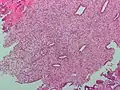

Endometrioid adenocarcinoma from biopsy. H&E stain. -

Micrograph of decidualized endometrium due to exogenous progesterone. H&E stain. -

Micrograph showing endometrial stromal condensation, a finding seen in menses.